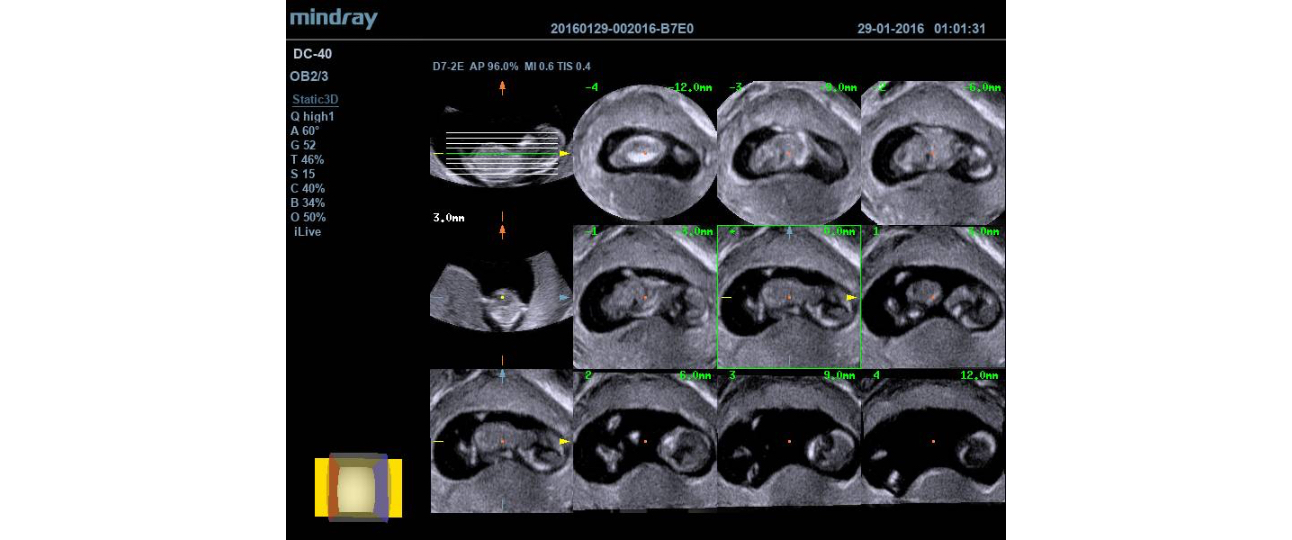

The DC-40 delivers a range of tools that maximize diagnostic accuracy. Covering General Imaging, OB/GYN and Cardiology, the DC-40 provides complete solutions including Natural Touch Elastography, advanced 4D imaging with iLive & iPage, Auto IMT, UWN Contrast Imaging, TDI & TDI QA, Free Xros M and FreeXros CM.

4D iPage